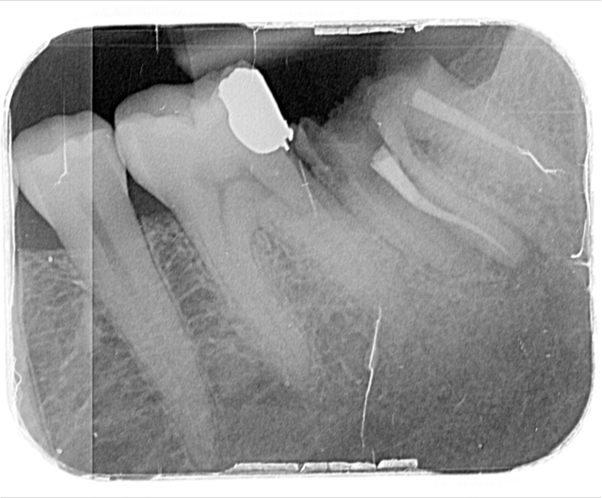

After three months the healing abutment was then removed. The presence of the healing abutment facilitated the development of an emergence profile from the implant platform during the healing phase. A fixture level impression was taken and a screw-retained crown with the screw emerging in the mid-occlusal area was fabricated. The crown was made on a zirconia framework on a hybrid base abutment layered with e.max ceramic with ultra-polished zirconia subgingivally.

The occlusal profile was carefully contoured to avoid overloading of the implant, but of course to still provide functional benefit.

The decision to choose a tissue level implant here will aid the long-term cleansability of this implant prosthesis and the peri-implant soft tissues. Tissue level implants take the so-called ‘microgap’ away from the level of the bone and have long been considered as favourably designed implants in order to maintain peri- implant bone levels and long-term implant health. The use of tissue level implants in the posterior zone where aesthetics are not crucial has been a popular approach of many implant dentists in the past due to the above mentioned benefits.

This case beautifully demonstrates the emergence profile that the tissue level implants facilitate along with the ease of cleansability for the patient, even when the prosthesis is placed posteriorly in difficult to reach areas.